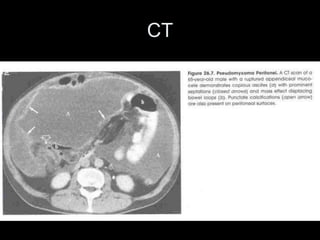

PMP : Diagnoses

• CT :

• Central displacement

of the small bowel and

compression of

retroperitoneal

structures

• Peritoneal cavity full of

PMP